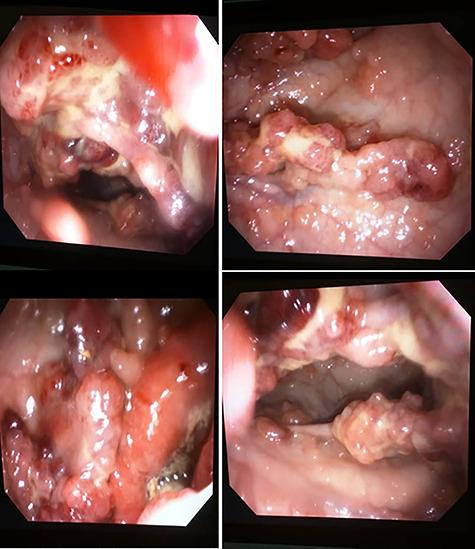

Familial adenomatous polyposis (FAP) is an inherited syndrome characterized by several adenomatous polyps of the gastrointestinal (GI) mucosa. If treatment is not provided, an average individual with classic FAP will develop colorectal carcinoma around the age of 40 years. The incidence rate of FAP in developing countries like Ghana is unknown compared to advanced countries. We present the first FAP case of a 22-year-old Ghanaian female who presented with massive lower GI bleeding and underwent surgical management after a thorough investigation. The initial assumption that colonic polyps are scarce in native Africans may be more than what is perceived. This highlights the need for the availability of endoscopic services in Ghana.

家族性腺瘤性息肉病(FAP)是一种遗传性综合征,其特征为胃肠道(GI)黏膜出现多个腺瘤性息肉。如果不进行治疗,典型FAP患者平均会在40岁左右患上结直肠癌。与发达国家相比,在加纳等发展中国家FAP的发病率尚不清楚。我们报告了首例22岁加纳女性FAP病例,该患者出现大量下消化道出血,经过全面检查后接受了手术治疗。最初认为非洲本地人结肠息肉罕见的假设可能比人们所认为的情况更为复杂。这凸显了加纳提供内镜检查服务的必要性。